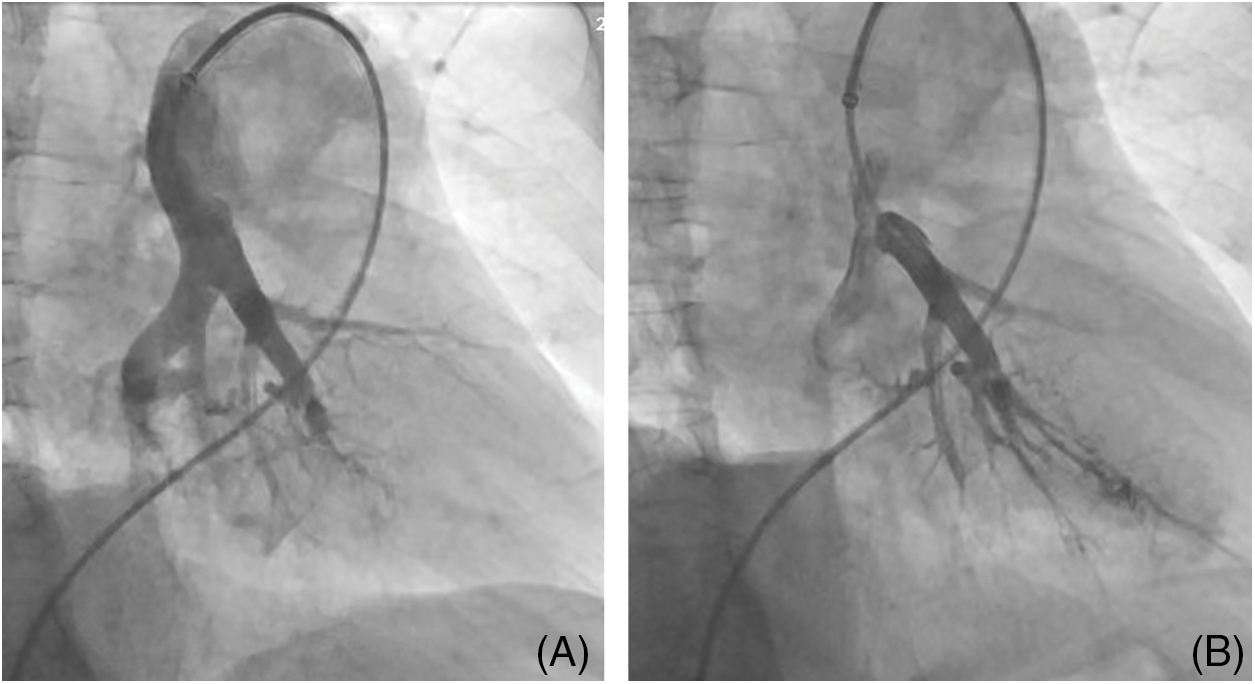

DSA is used to diagnose CTEPH and evaluate therapeutic indications for pulmonary vascular surgeries, such as PEA or BPA (Fig. 3). In light of the development of CT technology, C-arm CT (CACT) of the pulmonary artery DSA may improve diagnostic work-up for patients with CTEPH by providing additional information through identifying more vessels as prospective BPA targets and giving guidance, especially before surgery or intervention [32,33].

Figure 3: A patient with chronic thromboembolic pulmonary hypertension underwent balloon pulmonary angioplasty (BPA). (A) DSA of the pulmonary artery prior to BPA procedure, (B) DSA of the pulmonary artery post-BPA procedure